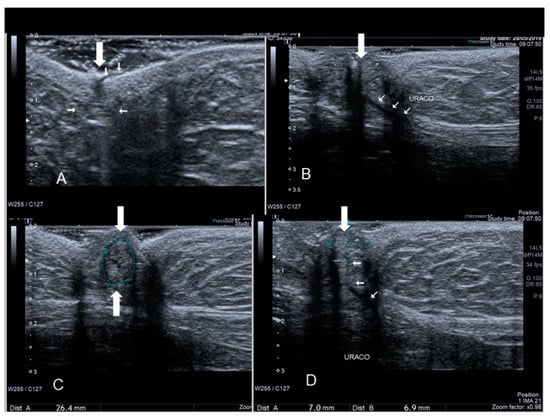

Figure 21. Diaphragmatic endometriosis (see white arrow) confirmed at surgery (A,B).

3.6. Thoracic Endometriosis

Thoracic endometriosis (TE) is an endometriotic lesion that involves the diaphragm, pleura, and/or lung. Lung is rare, but diaphragm lesions are not so rare [5,7,32]. The typical manifestation of diaphragmatic endometriosis is catamenial pneumothorax. Usually the diagnosis is performed using MRI in the absence of reports regarding ultrasound findings. Diaphragmatic endometriosis is characterized by ultrasound as small hypoechoic lesion (Figure 20 and Figure 21).